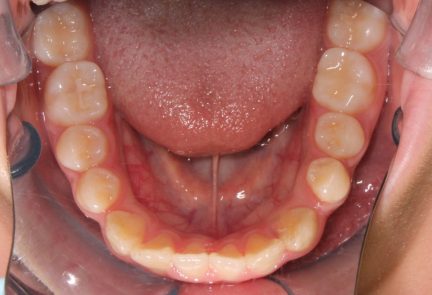

Classe III, articulé postérieur, articulé antérieur, occlusion bout-à-bout, béance, arcades asymétriques, déviation de la ligne médiane mandibulaire, chevauchement, rotations, espacement

- Alignement des deux arcades par dérotation

- Forme de l'arcade améliorée

État initial